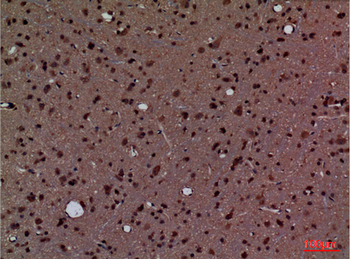

Anti-Cyclophilin A/PPIA Antibody [orb19174]

FC, ICC, IF, IHC, IHC-Fr, WB

Human, Mouse, Rat

Rabbit

Polyclonal

Unconjugated

10 μg, 100 μgCYPA Rabbit Polyclonal Antibody [orb100498]